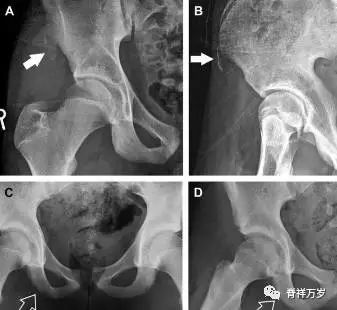

撕脱性骨折常在体育运动时由于肌肉强烈收缩引起。图 3 为容易发生儿童撕脱性骨折的部位。

图 3 儿童撕脱性骨折的危险区

图 4 儿童撕脱性骨折。正位片(A)和斜位片(B)示从髂前上棘撕脱的骨折碎片(箭头)。正位片(C)和另一个患者的蛙式位片(D)示右侧坐骨支皮质毛糙,腘绳肌腱撕脱损伤(如 C 和 D 空箭头所示)